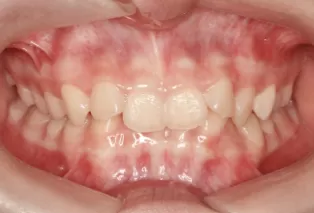

Intraoral photos